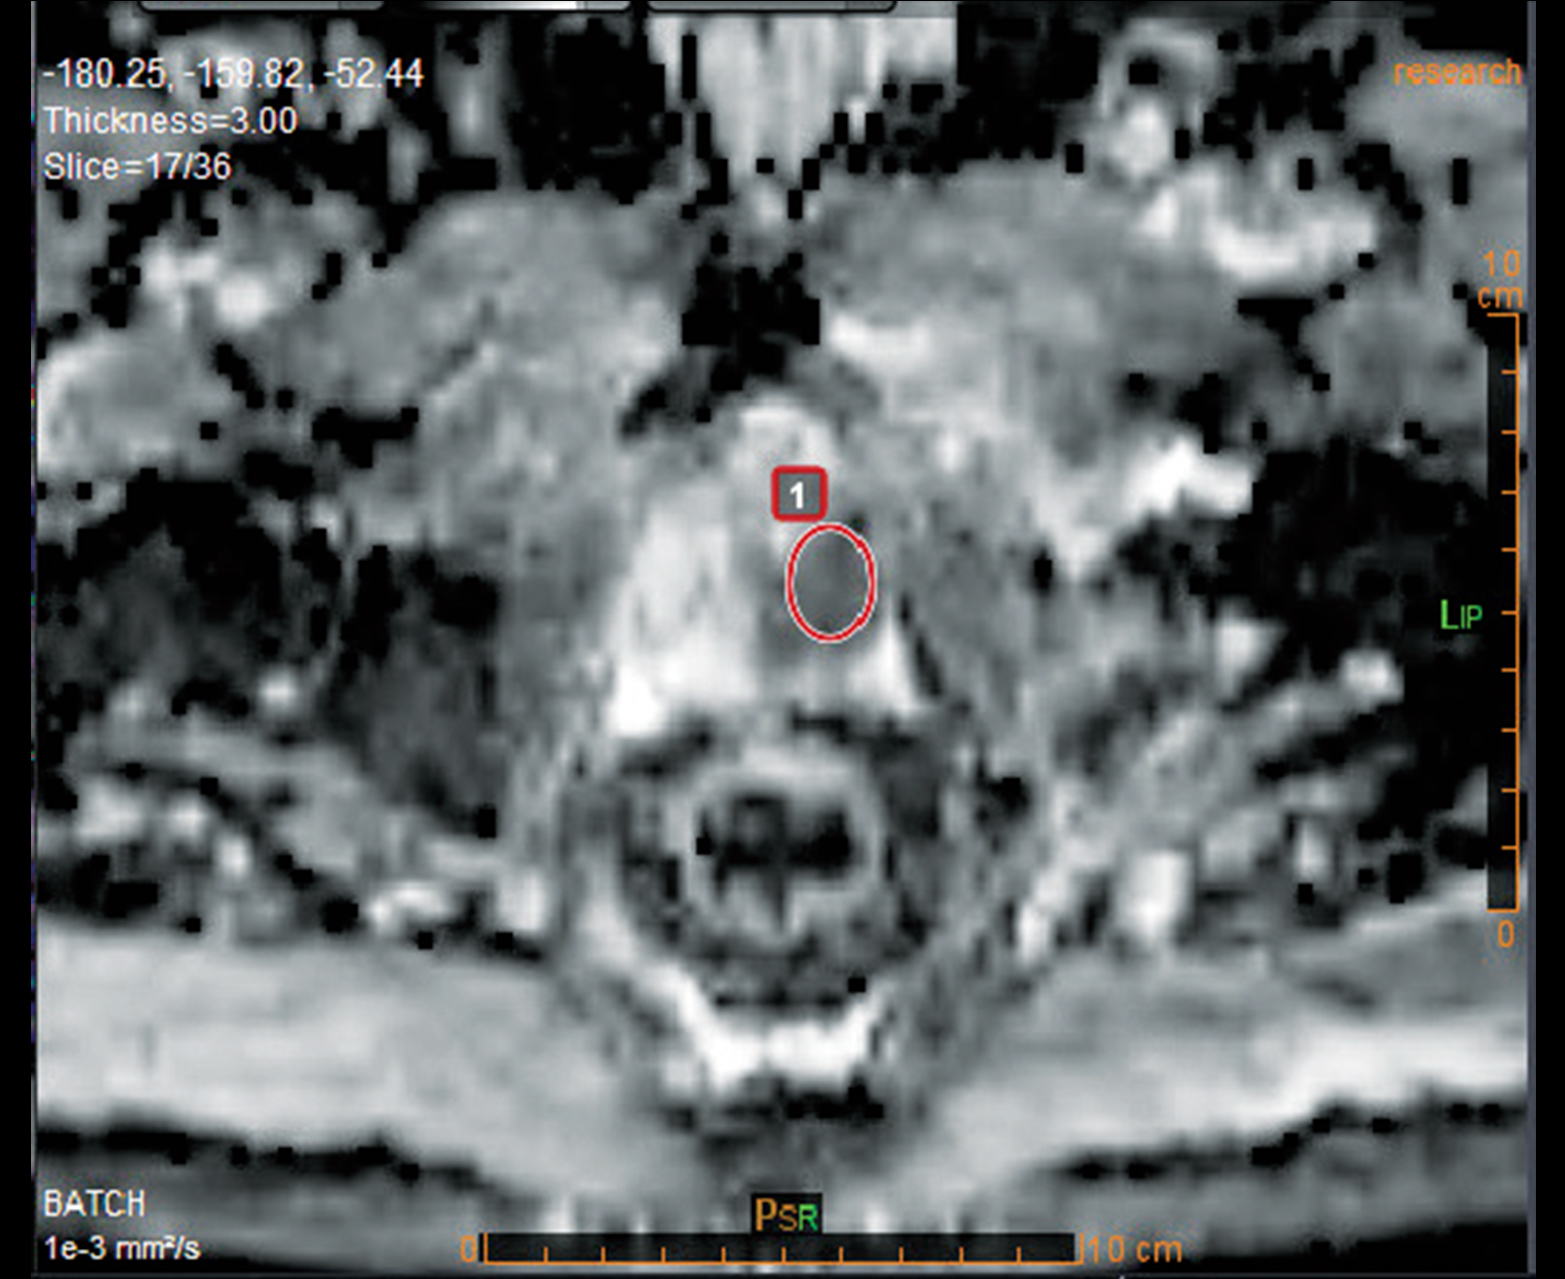

Расчет АЦП и других качественных и количественных карт

Многопараметрический просмотр и инструменты анализа для быстрой характеристики поражения

- Количественная оценка микроперфузии и электронных значений b методом IVIM